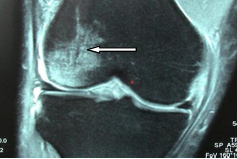

Les radiographies standards recherchent un pincement arthrosique d'un interligne, mais c'est l 'IRM qui est l'examen de référence des lésions ménisco-ligamentaires (Figure 6a). Il permet également d'analyser l'os sous chondral dont l'aspect plus clair (hypo -signal) est lié à une souffrance sur arthrose, nécrose ou après un traumatisme (Figure 6b).

Figure 6: fissure oblique de la corne postérieure du ménisque (a), œdème post-traumatique de l'os sous chondral du condyle externe (b)